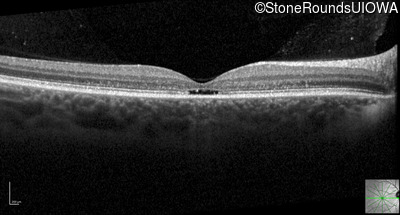

Optical Coherence Tomography - Right - 20/40 -2

Exemplar / OCT Stack

OCT Stack